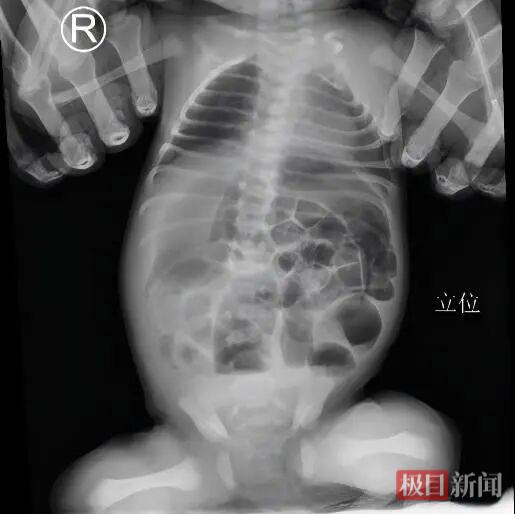

荆州市中心医院小儿外科牵头负责人田寅第一时间接诊,迅速为女婴进行了详细检查。结合临床症状与影像学结果,田寅很快锁定了“元凶”——先天性肛门闭锁伴直肠皮肤瘘合并肠梗阻。

这是一种新生儿消化道畸形,宝宝天生没有正常的肛门开口,并且直肠末端与皮肤之间存在一个通道异常,导致粪便无法正常排出,引发肠梗阻。田寅认为,这种情况如果不及时处理,肠梗阻会进一步加重,甚至导致肠穿孔,腹腔感染,随时可能危及生命。